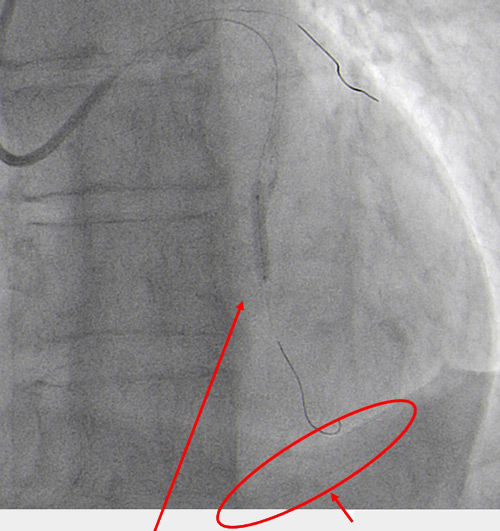

The angiographic control showed mild perforation recurrence (Figure 8.2).

Perforation still present (Figure 8.2)